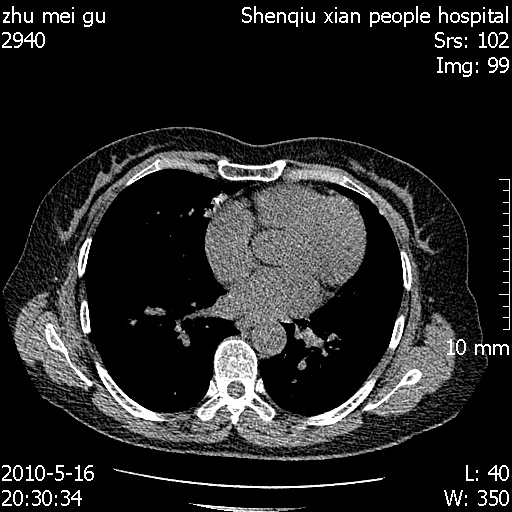

标题: CT26733:能否诊断支扩?

患者,女,62岁,有反复咯血史10年,近三年来大咯血数次,每次量在500-1000ml

图像不全。右中叶内侧段纤维、钙化灶。

没看到支气管扩张的证据

you右肺中叶有点支扩 但不至于咳那么多血啊

图像不全。右中叶内侧段陈旧性病灶。

右中叶内侧段慢性感染性病变,不排除合并支气管扩张可能。

建议hrct